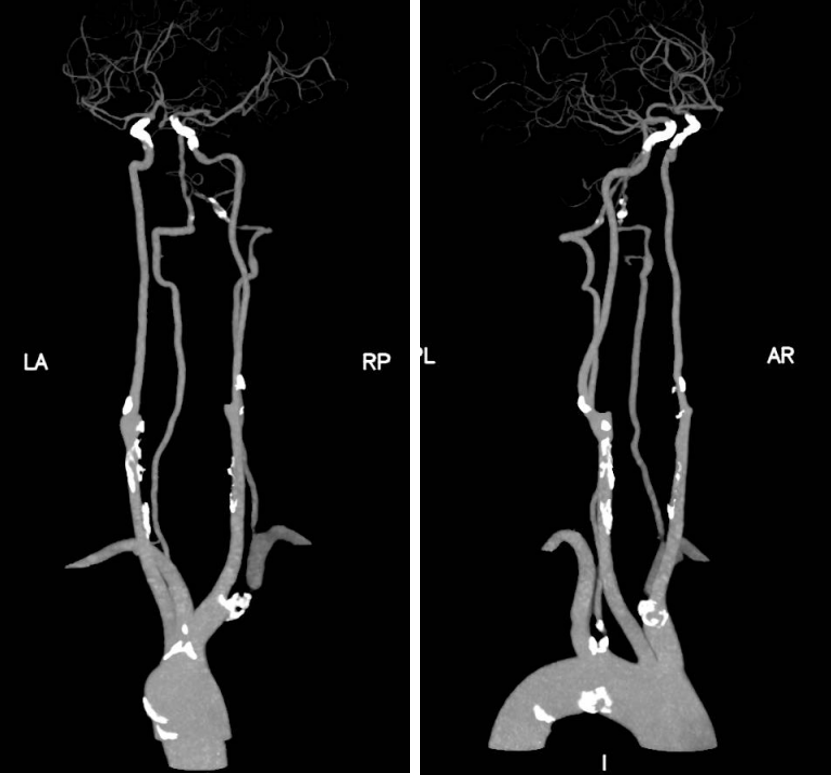

病例分享:

CEA同期颈动脉-椎动脉转流

患者信息:60岁男性,右手麻木无脉1年,伴高血压、糖尿病。

影像资料:右锁骨下动脉闭塞,右颈动脉狭窄,左椎动脉狭窄。

图:术前影像资料

手术方案:通过显露椎动脉、大隐静脉搭桥及同期CEA(术中三向转流),实现血运重建。